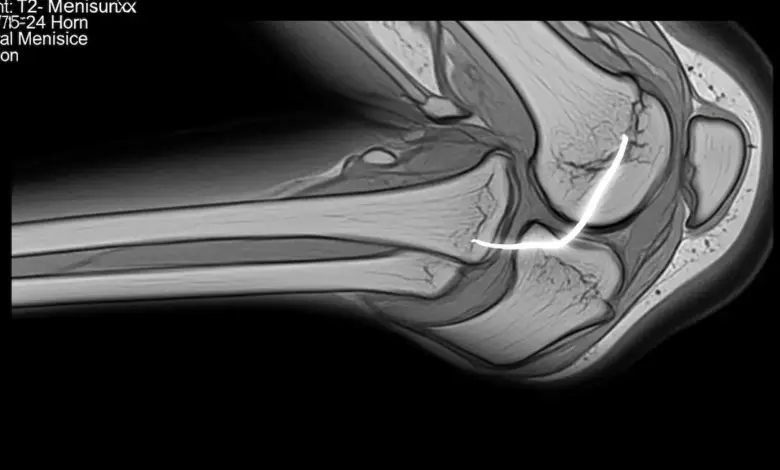

A meniscectomia parcial lateral é um procedimento artroscópico indicado para tratar lesões no menisco lateral quando a parte rompida não apresenta condições adequadas de reparo.

A meniscectomia parcial lateral consiste na retirada apenas do fragmento lesionado e instável do menisco lateral, com regularização da borda remanescente.

O procedimento geralmente é feito por artroscopia, com pequenas incisões e uso de câmera.

Durante a artroscopia, o cirurgião examina toda a articulação, identifica o padrão da lesão e retira apenas a porção rompida que está interferindo no movimento do joelho.